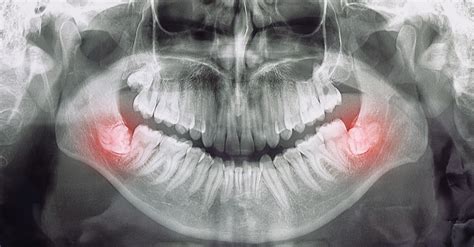

- Acude al dentista para una evaluación: En cuanto notes síntomas persistentes o fuertes, lo mejor que puedes hacer es visitar a tu odontólogo. Con una simple radiografía panorámica podremos ver la posición de la muela del juicio y determinar si hay espacio suficiente o no, si está torcida, si hay infección, etc. Personalmente, cuando recibo pacientes con dolor de cordales, lo primero que hago es esa evaluación radiográfica.

- Cordal retenida sin espacio: Si la radiografía muestra claramente que la muela no tiene espacio para salir o está chocando con el diente de al lado, es candidato seguro a extracción.

- Quistes u otras patologías: Como mencioné, rara vez se forman quistes alrededor de una cordal retenida. Si en una radiografía se aprecia una lesión quística asociada a la muela, la extracción junto con la limpieza de ese quiste es necesaria.

De hecho, muchas personas viven toda la vida sin cordales y no les afecta en nada su función dental. Solo recomendamos vigilar con radiografías panorámicas ocasionales: en algunos casos las muelas del juicio pueden estar dentro del hueso retenidas. Si no molestan ni dañan otros dientes, simplemente las dejamos allí. Y si ni siquiera existen, mejor aún, una preocupación menos.